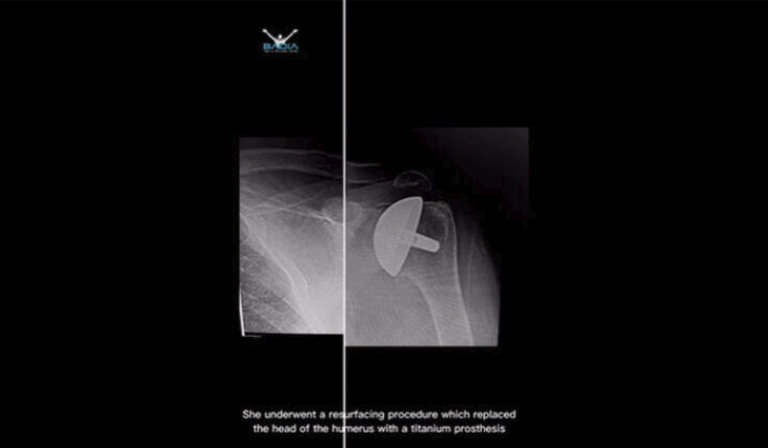

Paciente Colombiana Viaja a Miami Buscando la Solución de Entumecimiento y Hormigueo en Sus Manos

Muchos pacientes sufren por el dolor del síndrome del túnel carpiano por miedo a la cirugía Nuestra paciente Nelly estaba tan contenta con su primera liberación que 15 días después...